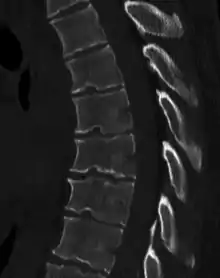

Scheuermann's disease on lateral CT of the T spine

Diagnosis is typically by medical imaging. The degree of kyphosis can be measured by Cobb's angle and sagittal balance.